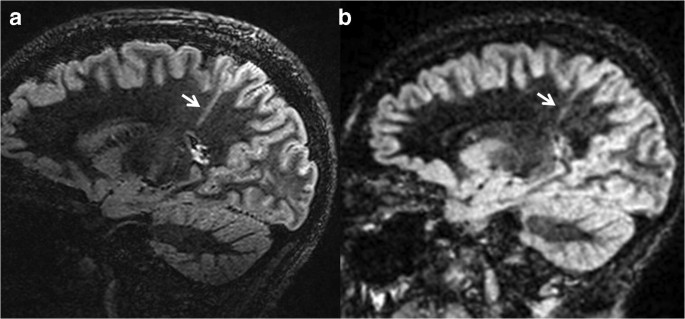

However, 7T MRI scanners are currently more expensive and less available in clinical and research centers To this end, we propose a method to generate superresolution 3T MRI that resembles 7T MRI, which is called as 7Tlike MR image in this paper Methods First, we propose a mapping from 3T MRI to 7T MRI space, using regression random forest7T MRI Knee Imaging Translational Research Towards Clinical Applications The virtual imaging workshop features an interactive format in which participants will experience realtime scanning of the knee at 7T and access to University of Minnesota imaging experts The workshop will appeal to MRI technologists who are interested in learningResults Susceptibilityweighted angiography 7T MR imaging can diagnose Parkinson disease with a mean sensitivity of 93%, specificity of 100%, and diagnostic accuracy of 96% 3T MR imaging

How much does a 7t mri cost- MAGNETOM Terra is the first 7T MRI scanner for diagnostic imaging and is designed for unprecedented breakthroughs in clinical care The unique Dual Mode lets you switch between clinical and research operations, with separate databases to distinguish between clinical and research scans This advanced ultrahighfield (UHF) technology has the potential to keep you at 7T MRI detected new lesions in over a third of 3T MRI nonlesional patients, confirmed and better characterized a 3T suspected lesion in one third of patients, and helped exclude a 3T suspected lesion in the remainder Our initial experience suggests that 7T MRI adds value to surgical planning by improving detection and characterization of

Fig 1 3T and 7T MRI The goal is to bring back the magnet to 117 T with all the MRI equipment, before the end of We will make our final adjustments in early 21, and plan to take the first image in AprilMay 21 – Metrolab You mentioned earlier that two other projects use a similar magnetic field but a smaller inner diameter The 7T MRI prototype sequences included xial and coronal 2D FLAIR sequences These sequences were repeated once again in case of intolerable head motion